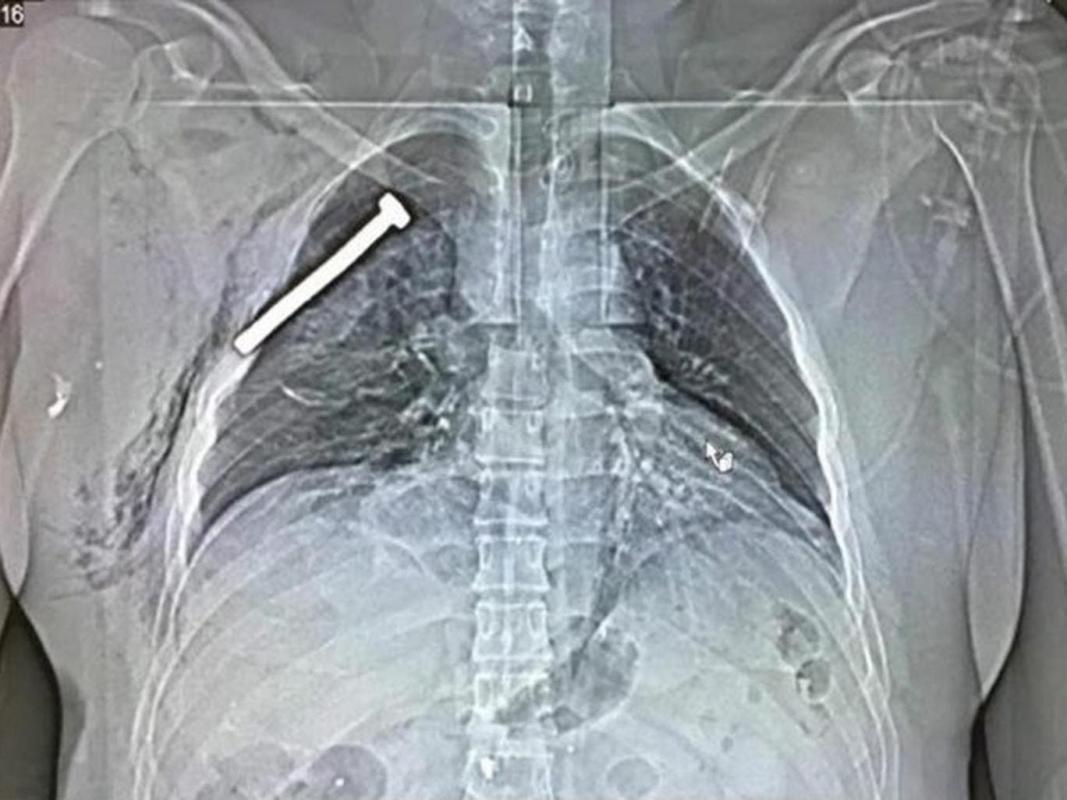

Impactante imagen de rayos X de una persona herida en el ataque terrorista de Bruselas

Una de las personas que resultaron afectadas por este hecho, el cual fue reivindicado por el grupo Estado Islámico, llegó hasta el Hospital Militar Neder-over-Heembeek donde se le prestó asistencia médica.

Lo "llamativo" del caso es que, mientras se le tomaban radiografías para evaluar su estado, se descubrió la presencia de un tornillo incrustado a la altura de su pecho.

La imagen fue difundida por el medio británico Independent y ya ha dado la vuelta al mundo..